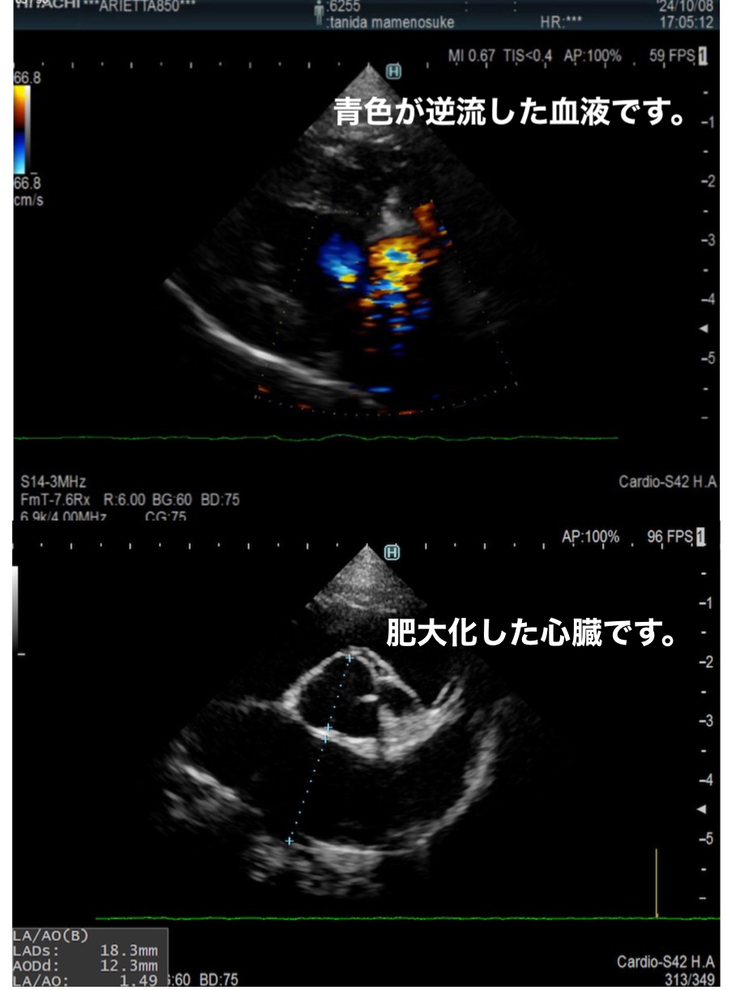

エコー検査やレントゲン検査をした結果、僧帽弁閉鎖不全症と診断されました。

⚫︎検査結果(一部)

⚫︎説明資料(一部)